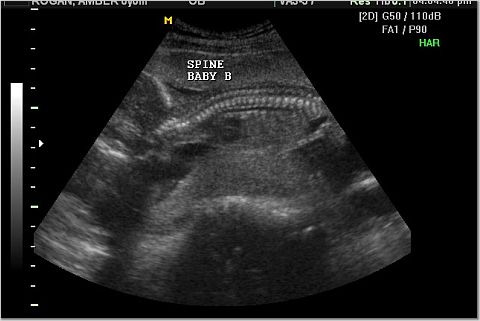

Pictures from Ultrasona

Baby A and Baby B Spine